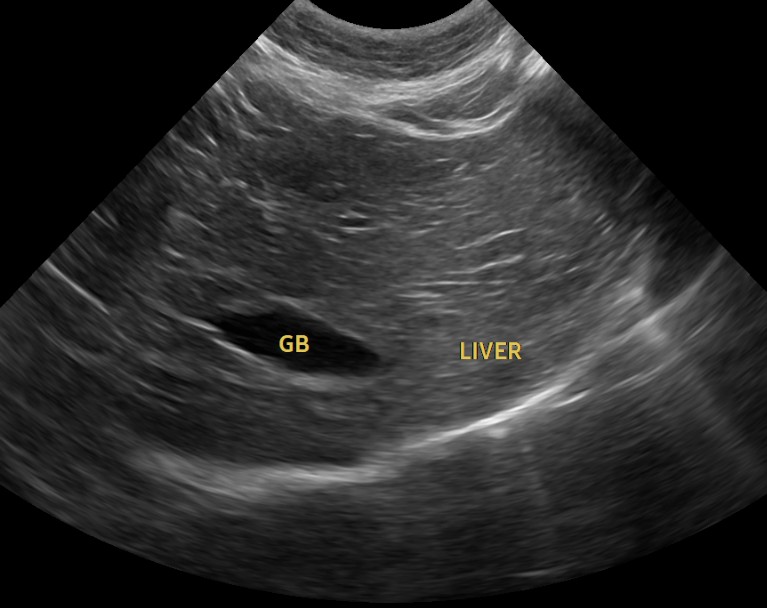

이번 아이처럼 특별한 증상을 보이지 않는 경우라도, 혈액검사·초음파·흉부 및 복부 영상검사 등을 한 번에 묶어 진행하면 현재 장기 기능을 객관적으로 확인하고, 잠재적인 질환의 방향성까지 파악할 수 있습니다.

혈액검사에서는 주요 장기 수치, 염증 수치, 전해질 균형 등을 확인했고, X-ray는 흉부·복부 전반의 장기 구조를 점검했습니다. 초음파는 장기 실질 구조나 미세한 이상까지 확인할 수 있어 검진의 핵심 항목으로 포함됩니다. 치과검사는 일반적으로 마취가 동반되어, 구강전용 엑스레이 촬영을 해야 정확한 판단이 가능하지만 치과전문 병원인 만큼 육안으로 기본적인 검사는 해드리고 있습니다.